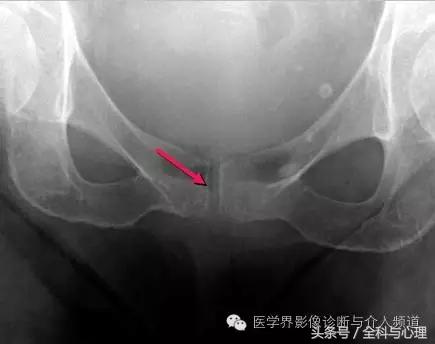

软组织钙化与骨化,软组织钙化和骨质增生 耻骨联合软骨钙化